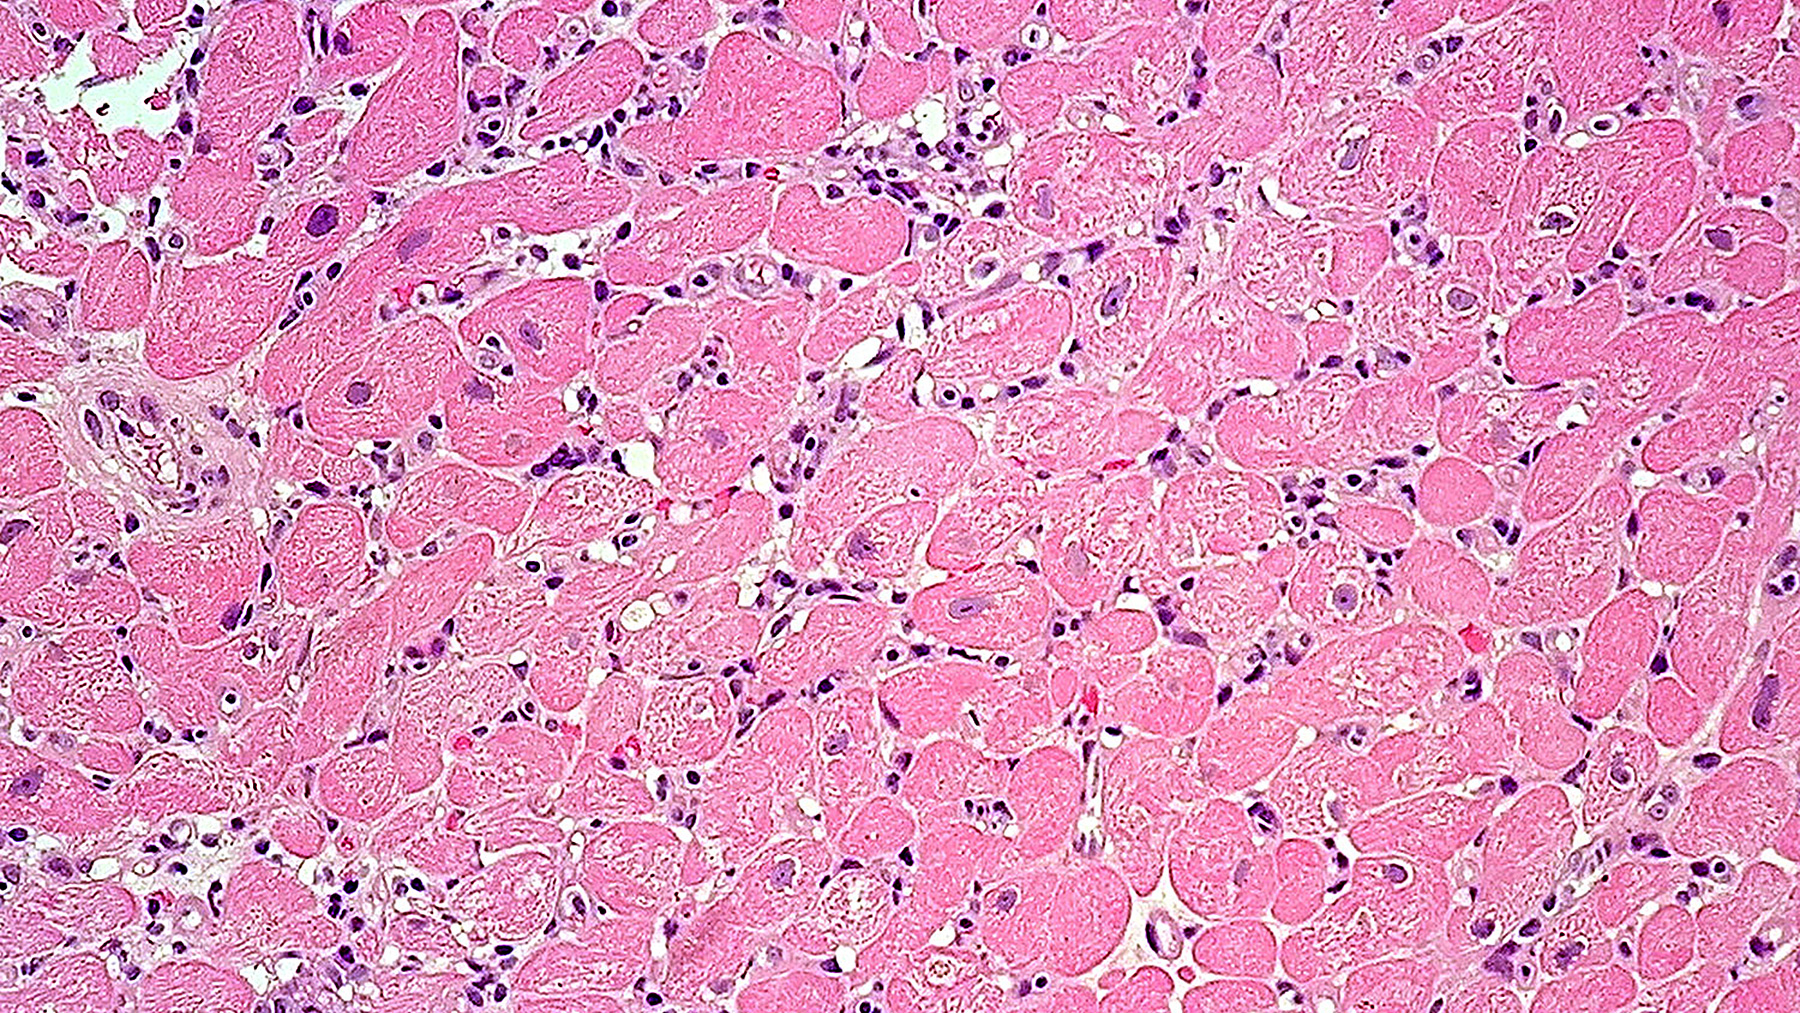

Figure E. H&E (20x) pAMR grade 1 (H+)

(Histopathologic AMR alone)